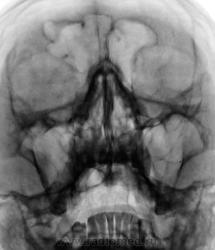

Медиальная стенка правой верхнечелюстной как-то не очень

А лобная справа что в себе несёт?

верхнечелюстных пазух. Да ещё пристеночное утолщение их стенок говорит в пользу их патологии.